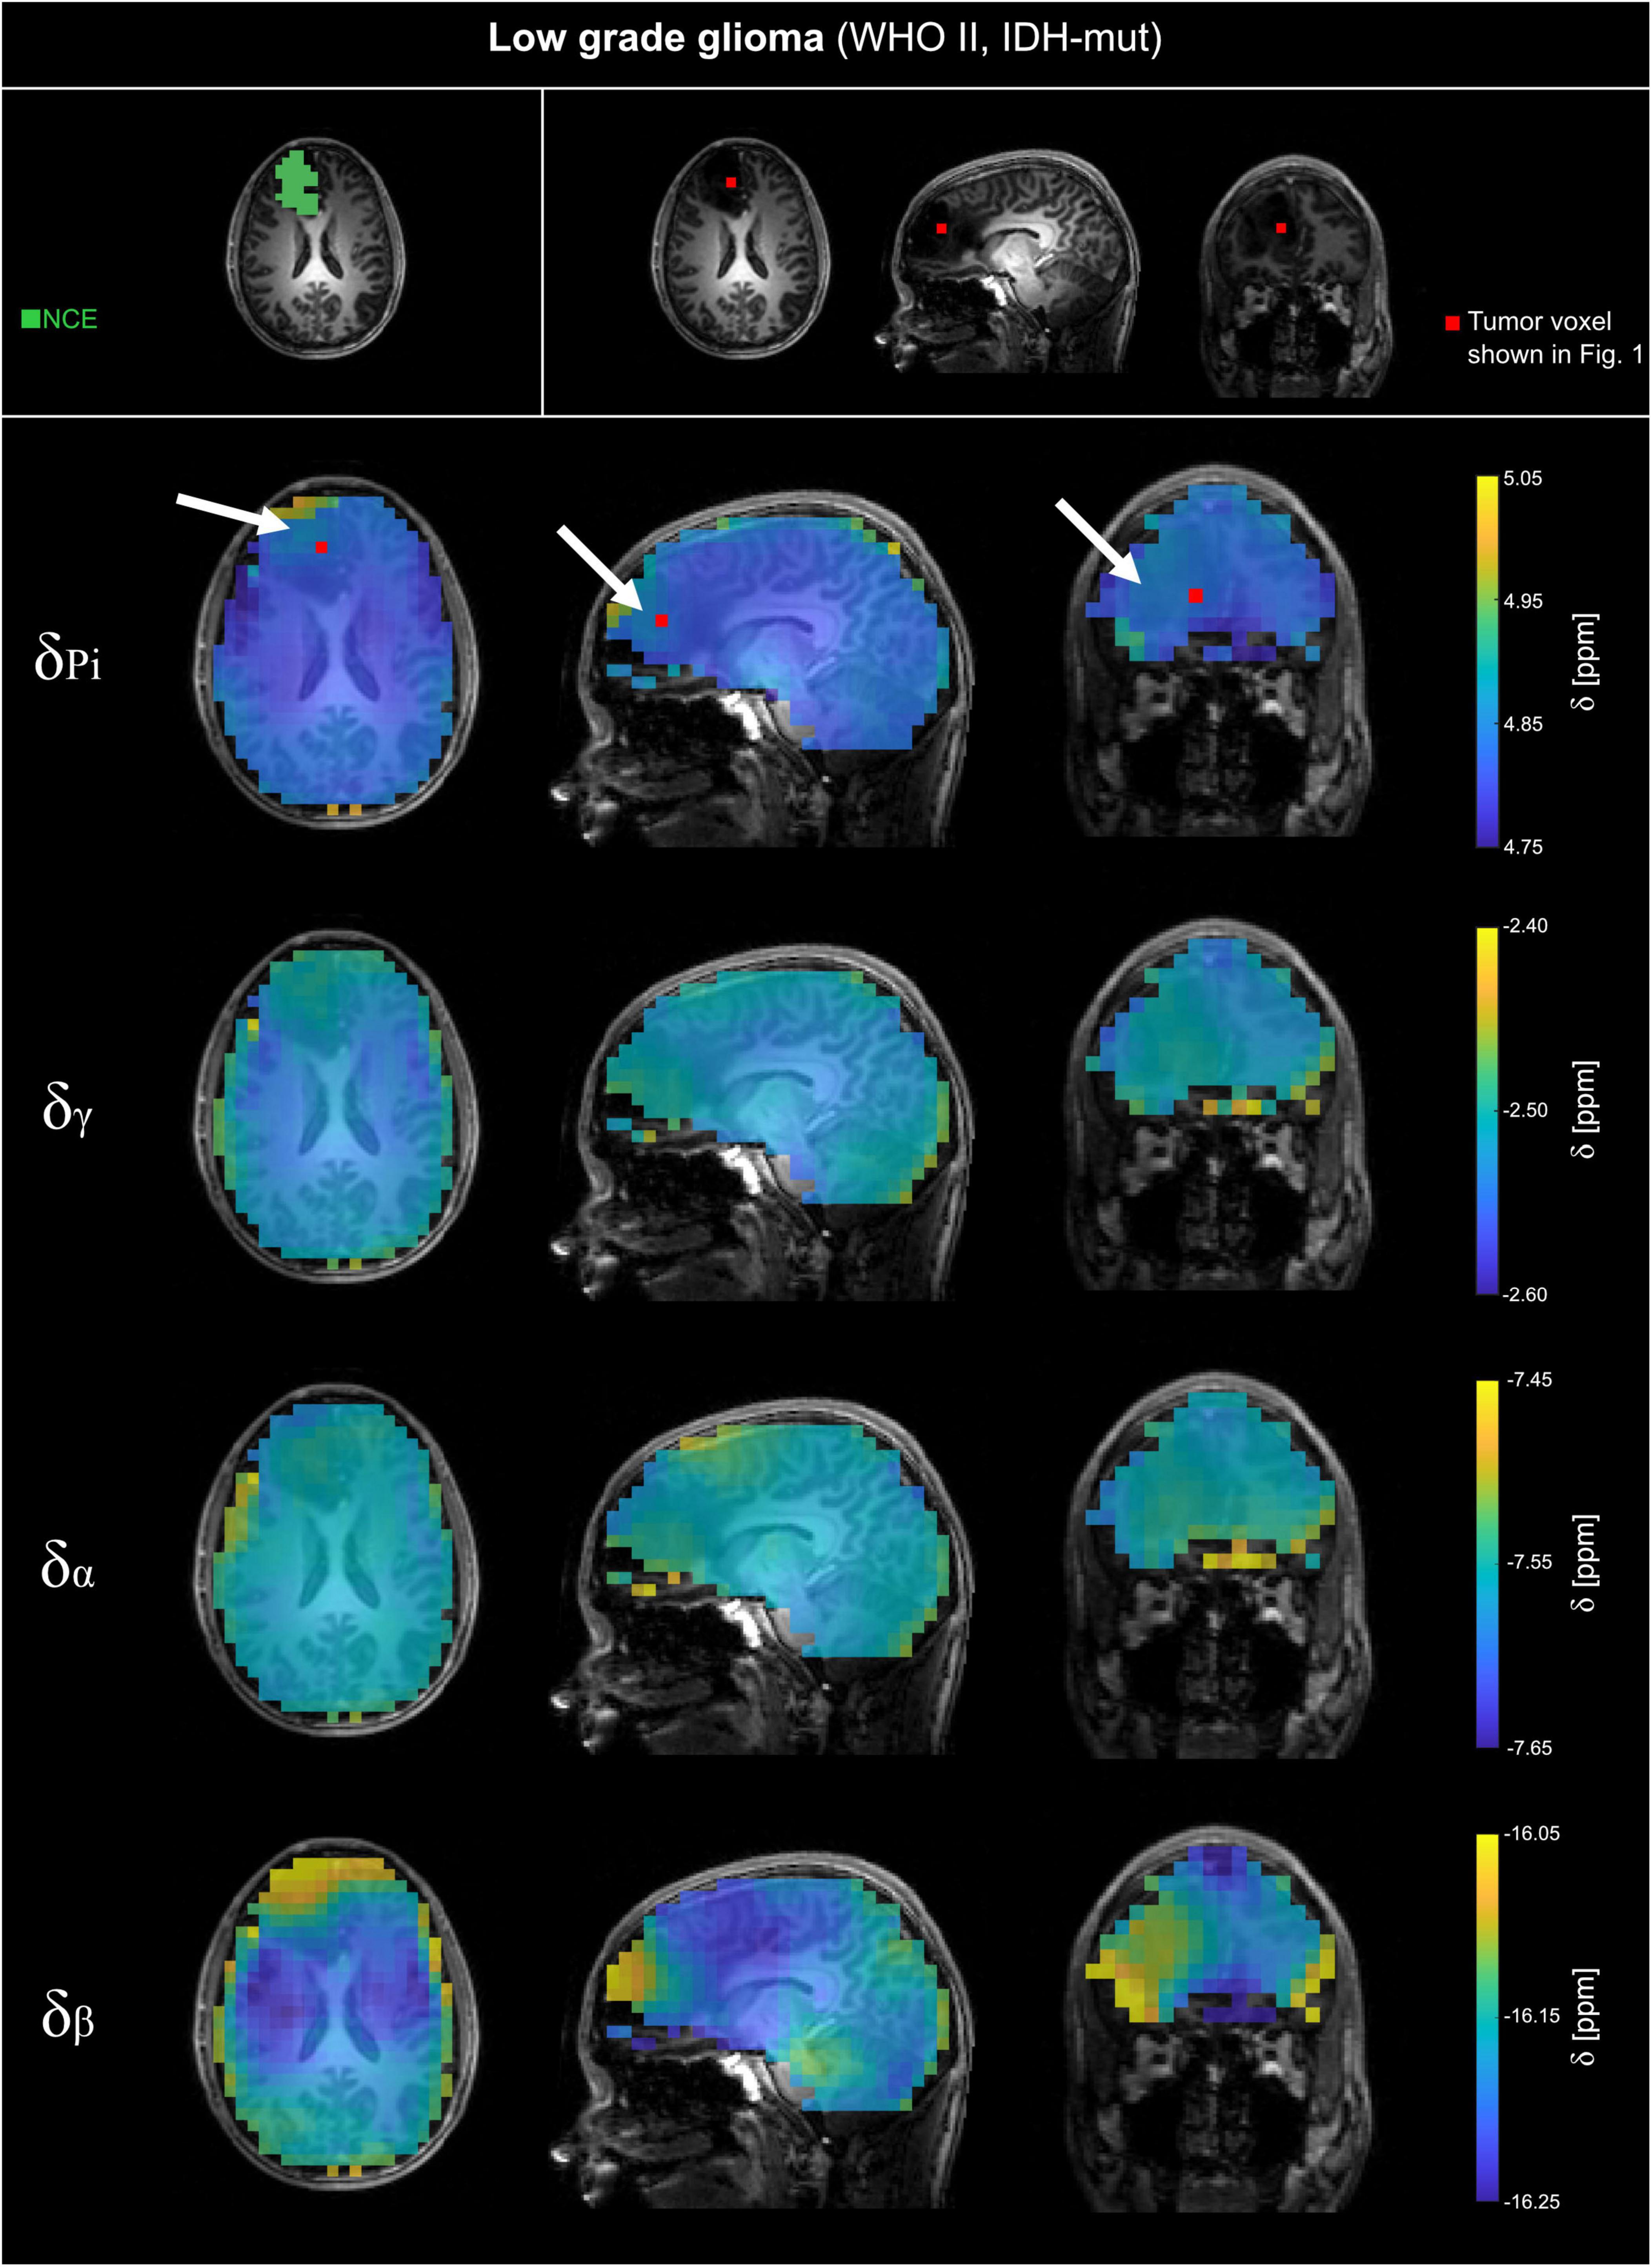

FIGURE 3

Volumetric maps of the quantified chemical shifts of inorganic phosphate (Pi) and ATP (γ-, α- and β-ATP) relative to phosphocreatine of a representative patient with low-grade glioma (WHO grade II, IDH-mut; LGG). The 31P MRSI datasets were acquired at B0 = 7T with an isotropic, nominal spatial resolution of (12.5 mm)3 and spatially zero-filled with a factor of 2 before quantification. The position of the tumor voxel shown in Figure 1 is indicated as red box on the slices of the anatomical image. On the top left, the regions of interests (ROI) used for further analysis are shown for a representative slice. For patients with LGG, the ROIs covering non-enhancing T2 hyper intensity (NCE) were analyzed. The position of the tumor is highlighted with a white arrow.

The analyzed 31P MRSI datasets from patients with glioma reveal differences in chemical shifts for different tissues, which are visible when comparing the acquired spectra (cf. Figure 1). The quantified chemical shifts of Pi and ATP (measured relative to PCr) show differences between tumor and healthy tissue (cf. Figures 1–3). The resonances of Pi, γ- and β-ATP obtained in tumor tissue are shifted downfield compared to those from healthy tissue. The α-ATP chemical shift shows minor differences between tumor and healthy tissue (maximal difference ≈ 0.05 ppm). For the chemical shifts of Pi, γ- and α-ATP, the difference between tumor and healthy tissue is smaller for the patient with low-grade glioma (LGG) than for the patient with high-grade glioma (HGG). Interestingly, this is not valid for the chemical shift of β-ATP, where the difference between tumor and healthy tissue of the patient with LGG (Figure 3), is comparable to the chemical shift difference for the patient with HGG (Figure 2). The difference in δβ between tumor and healthy tissue is up to 0.15 ppm for both patients. These qualitatively described observations are also confirmed in the following group analyses.

The comparison of the mean chemical shifts across the different tumor sub-compartments (Figure 4, left sections) shows particular patterns in the chemical shifts. For patients with HGG, δPi, δγ, δα and δβ are generally higher in the CE-ROI than in the EDM-ROI, with a significant difference for δPi (p = 0.014) and δγ (p = 0.004). For patients with LGG, δPi, δγ and δα are lower in the non-contrast enhanced ROI (LGG-NCE) compared to both HGG-GCE and HGG-EDM, but still higher than for healthy tissue. In contrast to that, for δβ, the shifts in the LGG-NCE ROI appear to be as high as the shifts in the HGG-CE ROI, supporting the observations from the representative datasets in Figures 1–3.